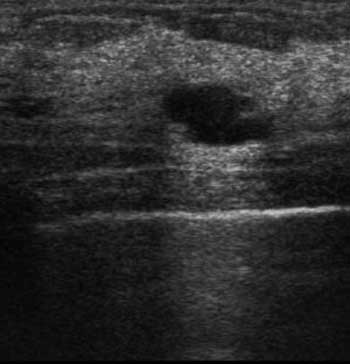

The target dataset was developed from 35 breast ultrasound scans that were segmented by an image-processing expert with extensive experience in breast lesion segmentation (the second author). The images, collected from the Web, are of different dimensions, ranging from to pixels (Figure 3, images resized for sake of illustration). These are the same images used to introduce EFIS originally [1].

Ultrasound images are generally difficult to segment, primarily due to the presence of speckle noise and low level of local contrast. It should be noted that the segmentation of ultrasound actually does require a complete processing chain, (including proper preprocessing and post-processing steps). However, the purpose of using these images was solely to demonstrate that the accuracy of the segmentation can be increased with the application of SC-EFIS.